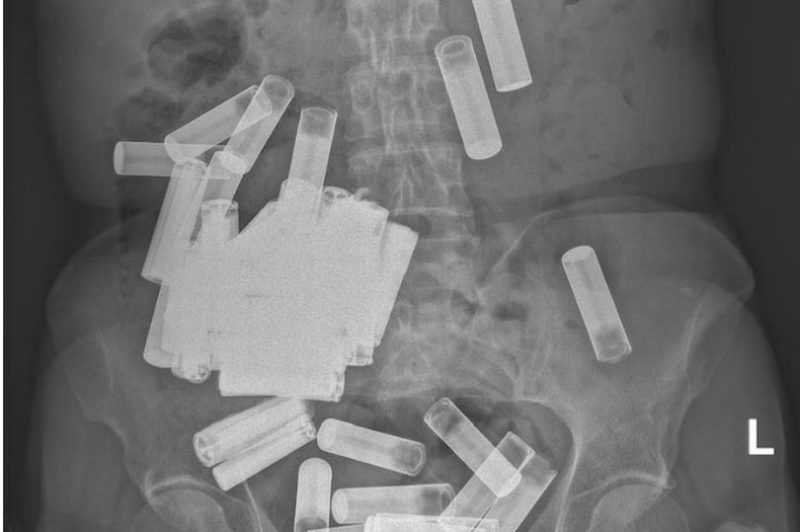

Uma mulher de 66 anos ingeriu 55 pilhas, conforme ocorrência no Hospital Universitário de St. Vincent, em Dublin, na Irlanda. As baterias estavam alojadas em seu estômago, com algumas localizadas no cólon. De acordo com os médicos, “infelizmente não é a primeira vez que isso acontece, mas este é o número mais alto de todos os tempos”.

Pilhas estava armazenadas no estômago da mulher – Foto: ReproduçãoPilhas estava armazenadas no estômago da mulher – Foto: Reprodução

Ela chegou nervosa e agitada ao hospital, reclamando de mal-estar. As baterias foram descobertas depois que um raio-X identificou objetos estranhos em seu corpo. Felizmente, nenhuma das pilhas estava obstruindo seu trato gastrointestinal. Assim, os médicos esperavam que ela expelisse naturalmente, relata a Live Science.

De acordo com a reportagem do Irish Medical Journal, a mulher conseguiu expulsar cinco AA’s – pilhas pequenas -na primeira semana. O restante, no entanto, ficou preso. Ela então sentiu cólicas estomacais e os médicos resolveram recorrer ao processo operatório.

Os cirurgiões agiram e removeram 46 das baterias restantes – deixando quatro ainda presas em seu cólon. Segundo o “Huffington Post”, os médicos adotaram prática de massageamento para estimular a expulsão dos objetos. Depois de alguns dias, todas as pilhas foram extraídas e a paciente pôde se acalmar.